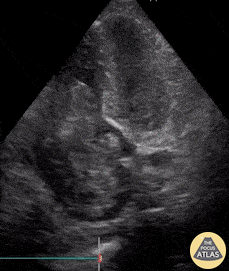

64 yo man with history of hepatic cirrhosis presented to ED with hypotension. During the RUSH exam, we incidentally identified this large hyperechoic mass occupying a large part of the right heart. Cardiac myxomas are the most common primary cardiac tumor in adults, though only 15–20% originate within the right atrium as does this one. The etiology of hypotension in our patient ended up being septic shock secondary to SBP. However, bedside ultrasound sometimes surprises you with stunning and unexpected images! Renato Tambelli, @JediPocus Emergency Physician (HCFAMEMA /Sao Paulo, Brazil)